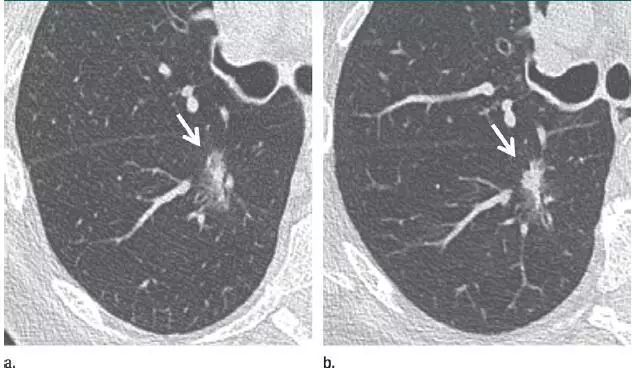

1. 错构瘤

图 1 层厚 1 mm 的 CT 横断面图像,(a)为肺窗,(b)为软组织窗,显示边缘平滑、内含脂肪和钙化的实性结节(箭头),符合错构瘤表现。不建议进一步 CT 随访。